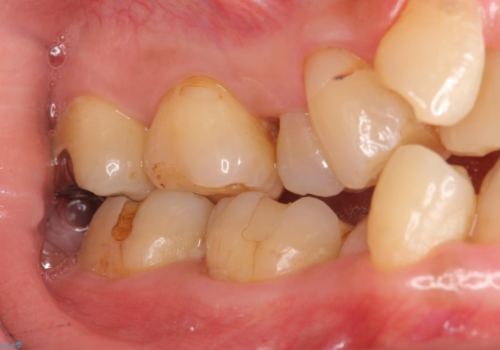

- 奥歯の詰め物のやり替えを希望して来院。

銀歯と、プラスチックをセラミックにかえました。

古い詰め物を取るときに、しっかり虫歯はとっています。

右上6番は詰め物が大きく、インレーではなくクラウンとしました。